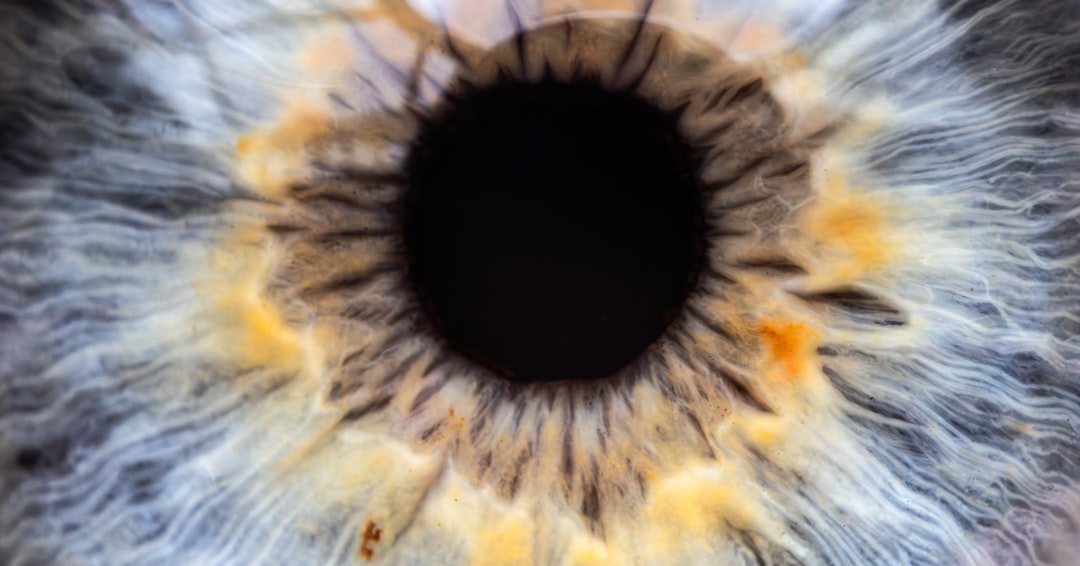

백내장 수술을 고려할 때 가장 먼저 걱정되는 부분 중 하나는 백내장 수술 비용입니다. 이 비용은 다양한 요인에 따라 달라지며, 병원의 위치, 수술 방식, 그리고 환자의 상황에 따라 차이가 날 수 있습니다. 일반적으로 백내장 수술은 몇 백만 원에서 시작하여, 사용하는 인공 렌즈의 종류에 따라 더 높아질 수 있습니다. 특히 다초점 렌즈를 사용할 시, 비용은 더욱 상승하게 됩니다. 따라서 여러 정보를 수집하여 비교하고, 가장 적합한 선택을 하는 것이 중요합니다.